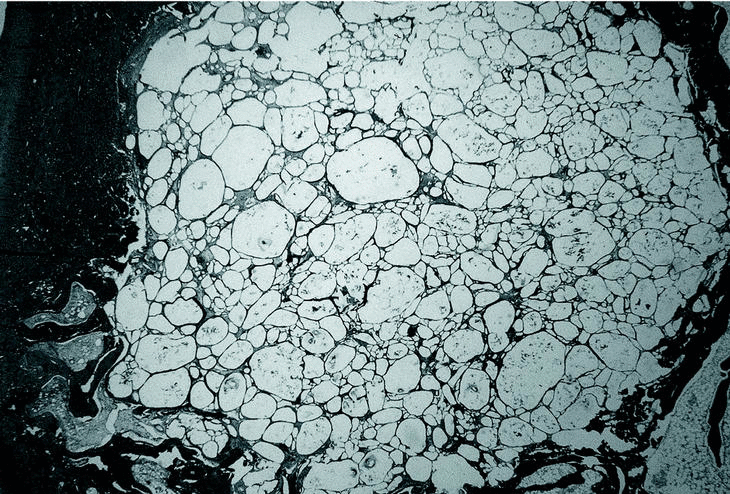

En los grupos PLA 80/20 (30.000) (fig. 1), PLA 80/20 (60.000) (fig. 2) y PLA 50/50 (60000) (fig. 3) se observó escasa neoformación ósea con abundante material polimérico con pocos signos de reabsorción a las 12 semanas y tejido fibrótico intraimplante y periimplante entre los gránulos de polímero, con presencia de células gigantes multinucleadas.

Figura 1. Imagen correspondiente al grupo de ácido poliláctico (PLA) 80/20 30.000 a las 12 semanas, mostrando escasa neoformación ósea, abundantes gránulos de polímero y esclerosis ósea periimplante (Tric.,x10).